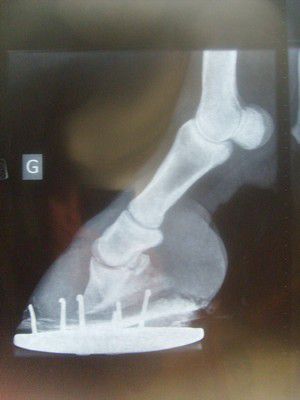

| Dire merci | Bonjour, J'ai récuperé un ps il y a un an, de gros soucis de pieds (anterieurs), il se tenait comme un fourbu. A son arrivée il a vu direct le véto qui l'a sondé, regardé sous toutes les coutures = il a de mauvais pieds, la corne pete, la sole est trop fine, faut ferrer... Il a vu 3 marechaux, tous ont tenu le meme discours : pas de pied, sole trop fine, on ferre (et moi bien sur j'ai pas cherché plus loin que leurs explications vaseuses )donc pendant 1 an il a été ferré, et effectivement, il allait très bien comme ca, mais mon but, c'était quand meme au final qu'il fasse enfin du pied, et que je puisse le mettre pieds nus comme les autres. J'ai retenté 6 mois plus tard, meme constat, aucune amelioration... puis encore 6 mois plus tard... pire ![]() du coup j'ai enfin percuté que ce n'etait pas possible, y avait un soucis la dessous, j'appelle le véto, on fait des radios : verdict la p3 a basculé sur les 2 anterieurs (ancienne fourbure sans doute )Alors pour le veto, c'est pas compliqué : il est comme ca, il restera comme ca Pour le marechal : on pose des fers en M, on tombe petit a petit la paroi, et on voit comment ca évolue ( on a tenté, il ne pouvait absolument pas marcher avec cette ferrure, donc virée au bout de 24h !) Finalement il est pieds nus dans des chaussons pour l'instant et la ca va a peu près ... Par contre dès que j'enleve les chaussons, il reprend sa posture de fourbu et ne bouge plus ... J'ai tel à une pareuse naturelle dans mon coin, elle peut venir le 12 octobre, mais n'a pas l'air sur de pouvoir faire quelque chose... J'ai tel a un autre, trouvé sur internet, qui lui m'assure pouvoir le soulager très vite, et remettre tout d'applomb en moins de 6 mois, en faisant une alvusion de la paroi en pince... cette meme personne me dit, au vu des radios, que la bascule ne vient pas d'une fourbure, mais d'une mauvaise vascularisation du pied entier, et que je dois mettre du cothivet sur tout le pied en attendant sa venue ... dans 3 semaines.... Je ne sais plus quoi faire, personne de competent dans les parages, trop d'avis differents ![]() en attendant j'ai pas mal coupé la pince qui etait trop longue et partait en babouche (le marechal laissait pousser pour qu'il "prenne du pied", mais on voyait bien que ca partait pas dans la bonne direction !) si il y a sur le forum des gens capables d'interpreter a peu près des radios, et les photos qui vont suivre, merci de m'aider, ou plutot, merci d'aider mon kéké ![]() |

| Dire merci | radio de face, anterieur gauche : [url=https://www.1cheval.com/membre/services/photos/images/103924.jpg] ![]() [/url] profil anterieur gauche : [url=https://www.1cheval.com/membre/services/photos/images/103925.jpg] ![]() [/url] anterieurs juste apres deferrage et avant coup de rape en pince : [url=https://www.1cheval.com/membre/services/photos/images/103926.jpg] ![]() [/url] [url=https://www.1cheval.com/membre/services/photos/images/103927.jpg] ![]() [/url] |

| Dire merci | ![]() marinaagen, j'ai une grande fourbue à la maison, que j'essaie de récupérer, alors ce que je sais de la fourbure 1) il te faut découvrir la raison/cause de la fourbure, pour éviter que le cheval ne revienne dans ce schéma, savoir si c'est dû à un trop de nourriture trop riche (PS parfois un peu trop avoiné aussi), si émotionel, stress, nervosité, angoisse, contrariété, etc médicamenteux etc. 2) parer juste, c'est mieux. sur ta photo ci-dessus le pied d'un fourbu pousse selon un angle différent vu la bascule de la phallange, il te faut donc regarder le haut du sabot, juste à la naissance de la couronne, sous les poils, et prolonger l'inclinaison de la paroi selon la première partie, 10cm sous les poils, et éliminer tout ce qui vient en avant de cette ligne sur ta radio, on voit bien l'angle de la phallange en pince allant vers le sol, et l'écartement de la parois, tu dois redonner une ligne de paroi parallèle à la phallange, ensuite, en dessous, la phallange doit être parallèle au sol et non relevé vers les talons, donc abaissé "doucement" les talons. attention, un fourbu peut avoir des soucis aussi d'usure des phallanges, d'abcès non détecté (dû à la bascule de la phallange et à la compression des chairs internes) et des soucis de tendons. à déterminer mais, d'une chose est sure, une année complète pour refaire une paroi depuis le haut à la couronne, et que le tout soit remis dans le bon sens, il faut donc être constant et patient. |

| Dire merci | Y a pire comme bascule, et au moins la phalange ne s'est pas trop effondrée et ça c'est pire que la bascule. Avec le pied nu tu pourras récupérer, ferrer n'a servi à rien avant alors autant arrêter. ![]() Il ne te reste plus qu'à tester les pareurs disponibles. ![]() Courage ce sera long. ![]() |

| Dire merci | rah c'est bête que les pieds de ma naine ont pas poussé suffisament pour refaire des radios, sinon j'aurais pu témoigner sur le fait que la phalange peut rebouger ou non. Il manque 2cm pour que la pince touche le sol et ça sera bon. Pour illustrer l'antérieur gauche de ma ponette en radio ![]() la meilleure décision que j'ai prise pour elle c'est de la passer pieds nus, depuis plus de boiterie sa sole s'est renforcée bon bien sur, sur terrain dur elle a des hipposandales mais plus de boiterie en tout cas. |